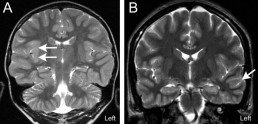

Focal cortical dysplasia (FCDs) are disease states diagnosed in childhood and adults. They are frequently associated with drug resistant severe epilepsy as well as with cognitive-behavioral deficits. Typically cortical lesions are isolated and range in their severity from mild cortical dyslamination without cytological abnormalities to severe dyslamination accompanied by dysmorphic neurons. For drug resistant forms, current treatments rely on surgical removal of the dysmorphic tissue however, this fails to remedy the symptoms in 30-50% of cases and can result inunpredictable cognitive side effects. Moreover, etiologies and pathophysiological mechanisms underlying FCDs are poorly understood.